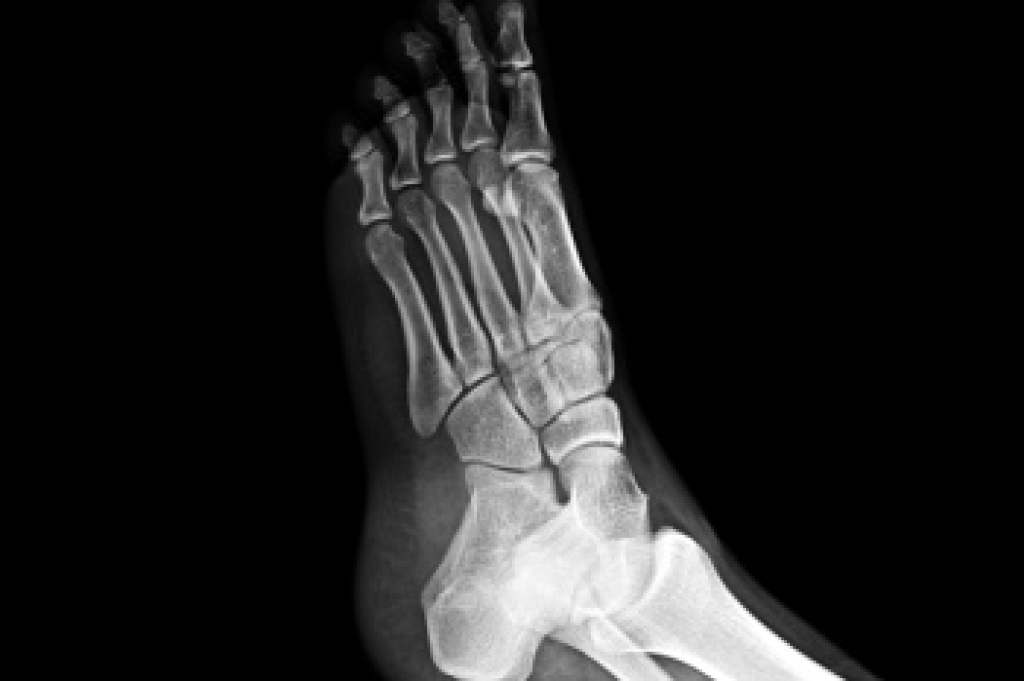

A diabetic foot ulcer is an open wound or sore that develops on the feet of individuals with diabetes. High blood sugar levels can damage nerves and blood vessels, leading to reduced sensation and poor circulation, which makes it harder for wounds to heal. Symptoms include redness, swelling, pain, and sometimes drainage or foul odor. Proper treatment is essential to prevent complications, such as infections or even amputation. Early care includes cleaning the ulcer, applying topical medications, and wearing special footwear to reduce pressure. In more severe cases, debridement, which is the removal of dead tissue, or surgery, may be necessary. A podiatrist plays a critical role in treating diabetic foot ulcers by providing wound care, recommending custom footwear, and monitoring the healing process. If you have diabetes and notice any foot sores or ulcers, it is suggested that you promptly schedule an appointment with a podiatrist to prevent serious complications.

Diabetes affects millions of people every year. The condition can damage blood vessels in many parts of the body, especially the feet. Because of this, taking care of your feet is essential if you have diabetes, and having a podiatrist help monitor your foot health is highly recommended.